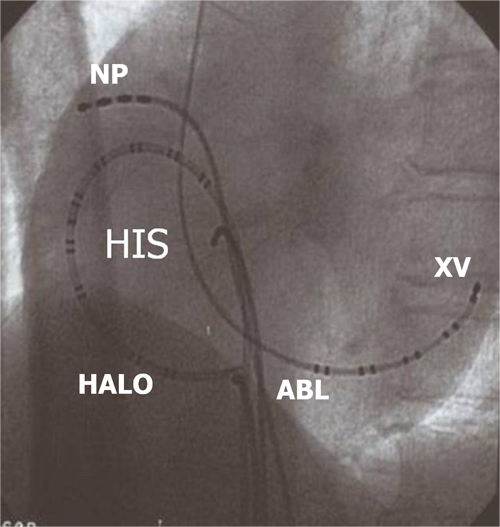

Điều trị cơn tim nhanh vào lại nút nhĩ thất dựa trên cơ sở việc triệt đốt một trong hai đường dẫn truyền qua nút nhĩ thất, đường nhanh hoặc đường chậm. Ngày nay, hầu hết các trung tâm tim mạch trên thế giới đều đồng thuận việc triệt bỏ đường chậm vì có tỉ lệ thành công cao hơn và ít biến chứng gây blốc nhĩ thất hơn. Ống thông đốt sẽ được đưa qua tĩnh mạch đùi tới vị trí triệt đốt đường dẫn truyền chậm ở vùng mô nhĩ phải nằm giữa bờ van hai lá và lỗ xoang tĩnh mạch vành, cách nút nhĩ thất khoảng 1-2 cm (còn gọi là vùng đáy tam giác Koch). Xác định vị trí đường chậm dựa vào điện đồ ghi được tại đầu điện cực đốt và hình ảnh giải phẫu trên X quang.

Hình 11: Vị trí các ống thông trên hình ảnh X quang trong triệt đốt đường chậm ở tư thế nghiêng trái 30 độ (trái) và nghiêng phải 30 độ (phải): NP: điện cực cùng cao nhĩ phải, His: điện cực vị trí bó His, XV: điện cực xoang vành, TP: điện cực mỏm thất phải, Abl: điện cực triệt đốt được đưa vào vùng đáy của tam giác Koch, dưới vị trí điện cực bó His khoảng 2 cm và ngang mức với lỗ xoang vành.